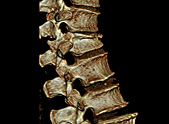

• Wirbelsäule

In der Neuroradiologie setzten wir die Computertomographie (CT) speziell ein zur Erstuntersuchung bei akuten Erkrankungen (Schlaganfall, Blutungen, Schädelverletzungen, Bandscheibenvorfall) und zur Nadelkontrolle bei der Entnahme von Gewebeproben (Biopsie).

Die CT-angiographische Darstellung der intrakraniellen Hirngefäße optimiert die sofortige Indikationsstellung zur Schlaganfall-Frühbehandlung mittels Lysetherapie. Diese bildgebende Methodik wird durch die Einführung der Perfusions-CT erheblich erweitert, das zusätzlich die Perfusionsverhältnisse in zirkulatorisch gestörten Hirnarealen aufzeigt.